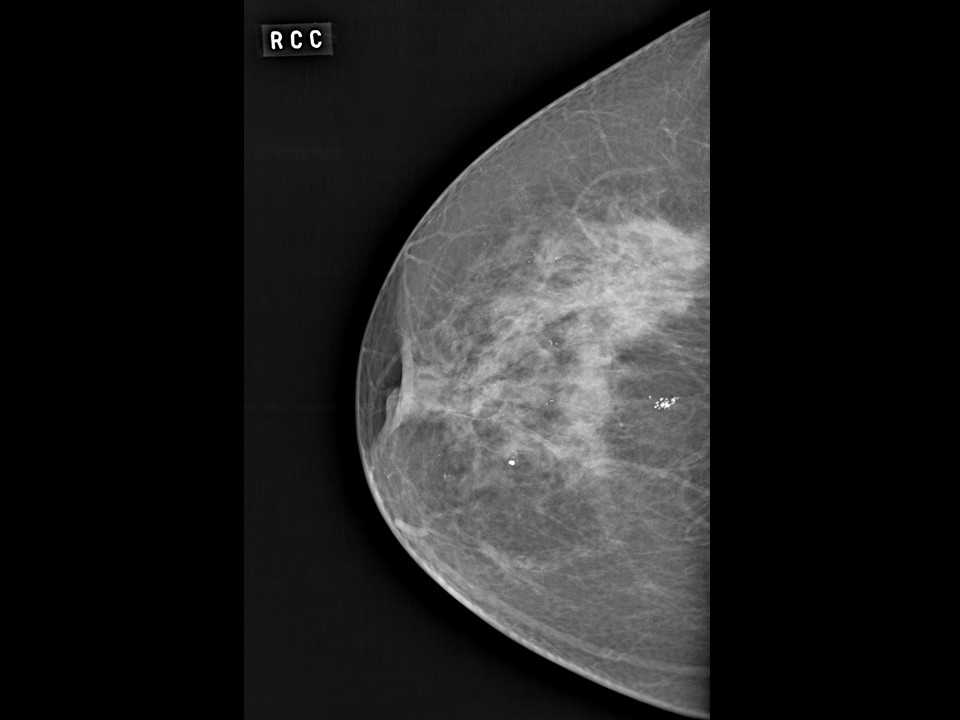

Феномен гипердиагностики в маммографии: примеры и иллюстрации

Раздел: Образы вокруг